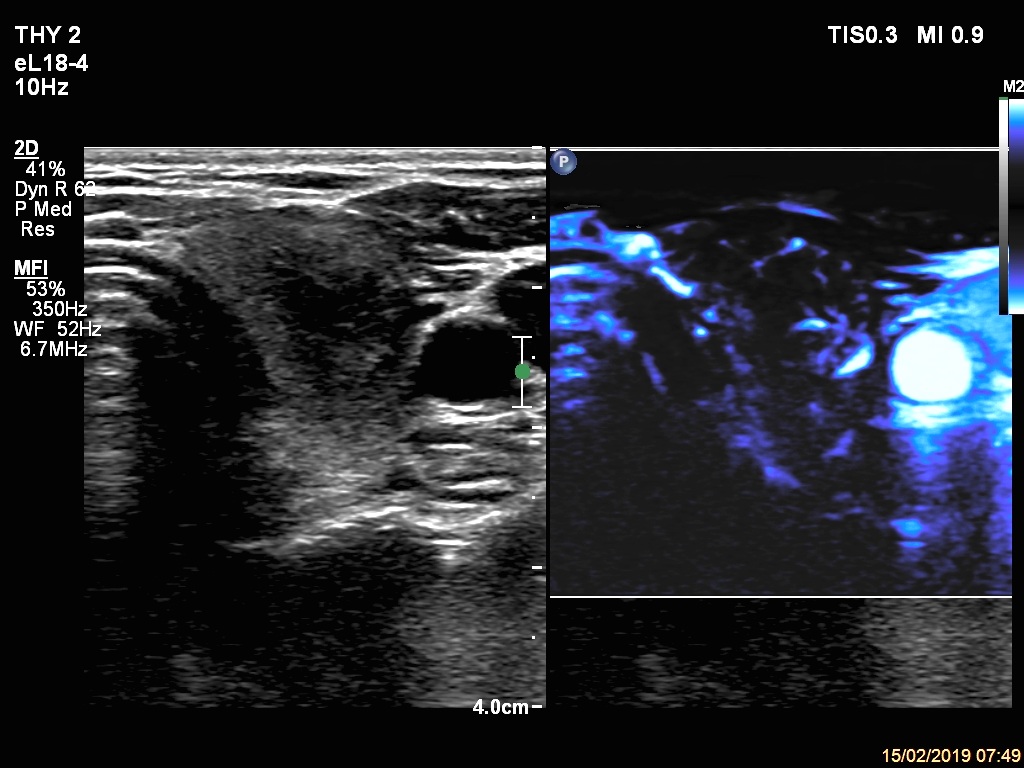

Right lobe, longitudinal scan

Upper part of the left lobe, transverse scan, microflow imaging.